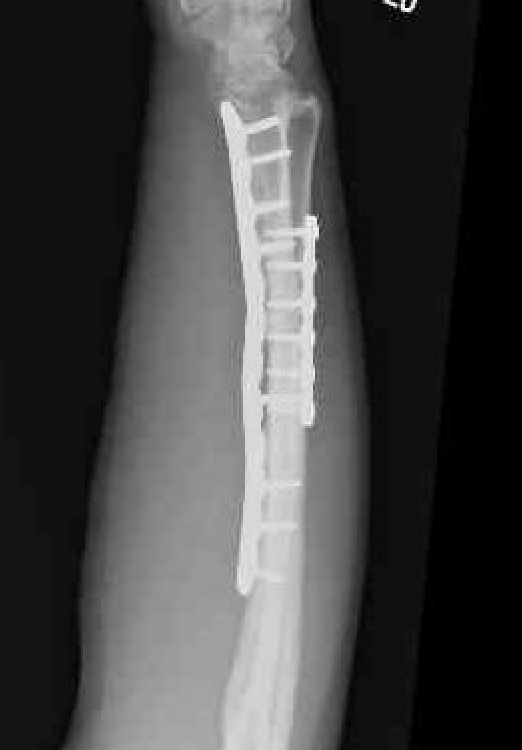

Galeazzi fracture

Galeazzi fracture with DRUJ disruption

Incidence of DRUJ instability after radius ORIF

Rettig et al J Hand Surg Am 2001

- 40 patients with Galeazzi fracture dislocations

- DRUJ instability after radius ORIF

- Type 1: radius fracture < 7.5 cm to articular surface: 55% DRUJ instability

- TYpe II: radius fracture > 7.5 cm to articular surface: 6% DRUJ instability